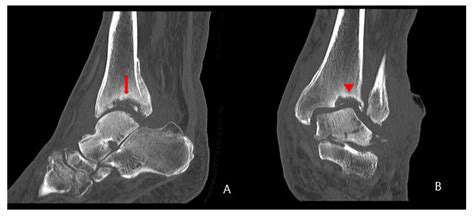

Imaging studies are essential for confirming the diagnosis and assessing the extent of the condition. Common imaging studies include:

• MRI (Magnetic Resonance Imaging): To assess soft tissue damage and inflammation

• CT (Computed Tomography) scans: To provide detailed images of bone structure

In some cases, a bone scan may be performed to detect areas of increased bone turnover, which can indicate active Charcot arthropathy.